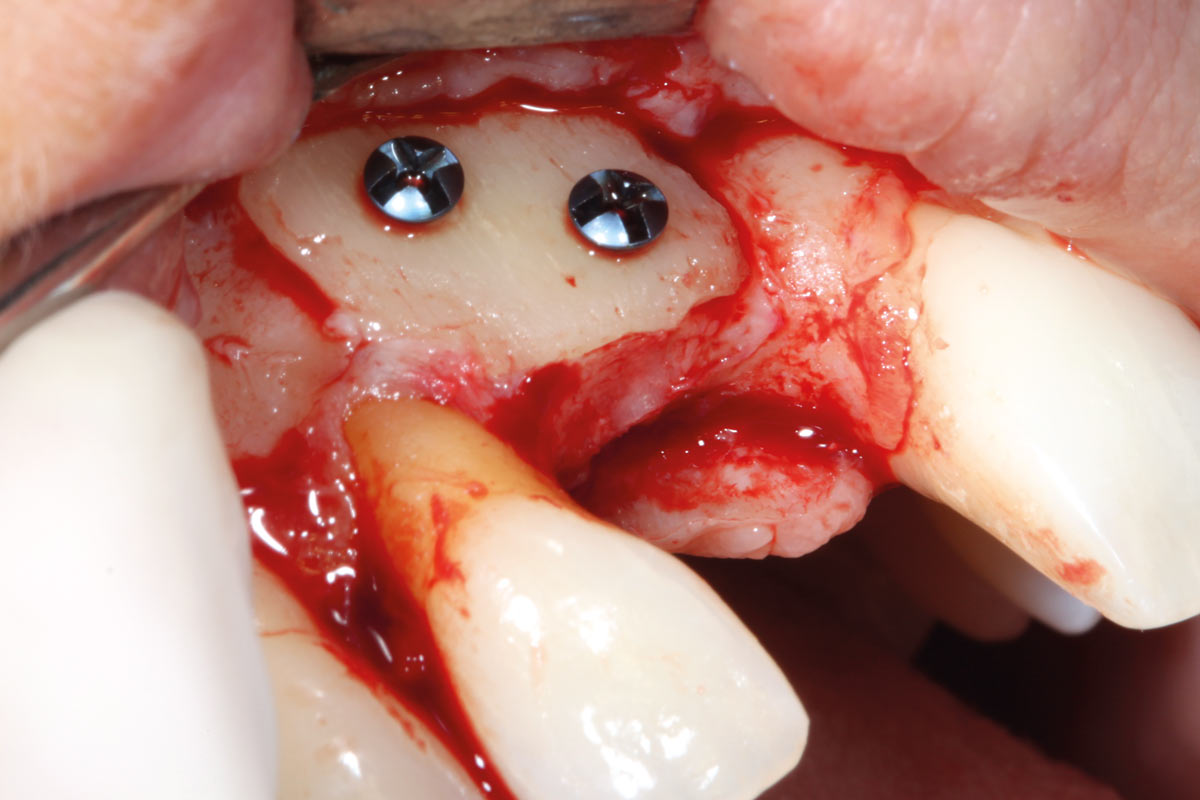

botiss cerabone® & Jason® membrane for horizontal augmentation - Clinical case by Dr. M. Steigmann